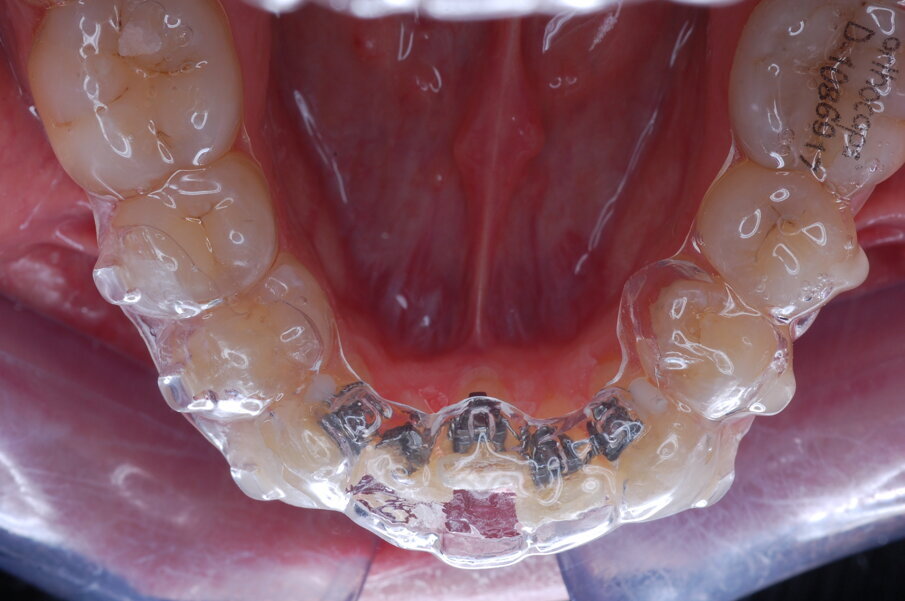

Diagnosi ed eziologia Un uomo sano di 39 anni si è presentato nel nostro studio ortodontico lamentando un aspetto dentale poco attraente e la paura della chirurgia ortognatica proposta da un altro ortodontista. Clinicamente, il profilo del paziente era rettilineo e la vista frontale non mostrava alcuna asimmetria facciale. L’esame funzionale non ha rivelato alcuna deviazione mandibolare o riduzione dei movimenti. Il paziente non aveva dolori articolari e non sono stati rilevati rumori articolari. Era presente una lieve occlusione molare bilaterale di Classe II, un morso aperto e un grave affollamento in entrambe le arcate. L’affollamento era particolarmente grave nell’arcata mandibolare, sebbene mancasse l’incisivo centrale mandibolare destro. Gli incisivi mascellari erano di piccole dimensioni, suggerendo una discrepanza dell’indice di Bolton se fossero stati presenti tutti e quattro gli incisivi mandibolari. Erano inoltre presenti un morso incrociato nella regione dell’incisivo laterale superiore sinistro e una grave rotazione distale del secondo premolare mandibolare sinistro (Figg. 1-8).

Figg. 1-8_Fotografie facciali e intraorali pre-trattamento.